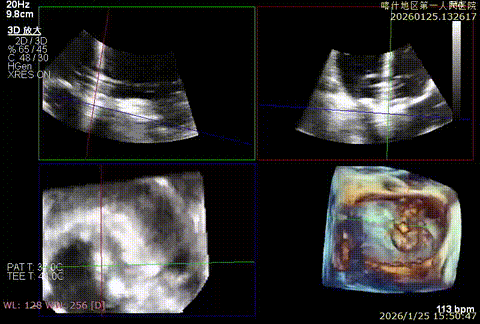

3D enface后叶栓系

3D enface观察反流

3D enface 观察脱垂